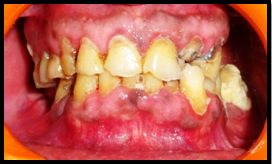

A 65 year old male patient reported to the outpatient department of Periodontology, SGT Dental College, Budhera with the chief complaint of bleeding gums, mobility of teeth and difficulty in mastication since one month. Patient also complains pain in relation to right back tooth region for 2 weeks. Pain was sharp in nature, aggravated on lying down, relieved by taking medication and was not referring to any other site. Patient gave past medical history of PCV since 2003 and on being medications for the same which included: Hydroxyurea- 500 mg twice daily as cytoreductive agent to decrease the leukemogenic risk and ecosprin -75 mg (low dose aspirin) to lessen the risk of thrombosis in an artery. Cimetidine was given (H2 receptor antagonists) to relieve gastrointestinal symptoms of peptic ulceration. Citrezine (antiallergic) was prescribed to relieve generalized itching which patient was suffering from. On intra-oral examination it was found that there was mobility present in relation to all the teeth, red inflammed gingiva with loss of stippling which bled profusely on slight provocation, generalized recessiongingival enlargement present in relation to all the teeth, attrition and root caries present in relation to 45. Patient was advised Orthopantogram (OPG) which showed generalized horizontal bone loss extending upto two third of root surface of almost all the teeth present (Figures 1&2).

Figure 2 Orthopantogram.